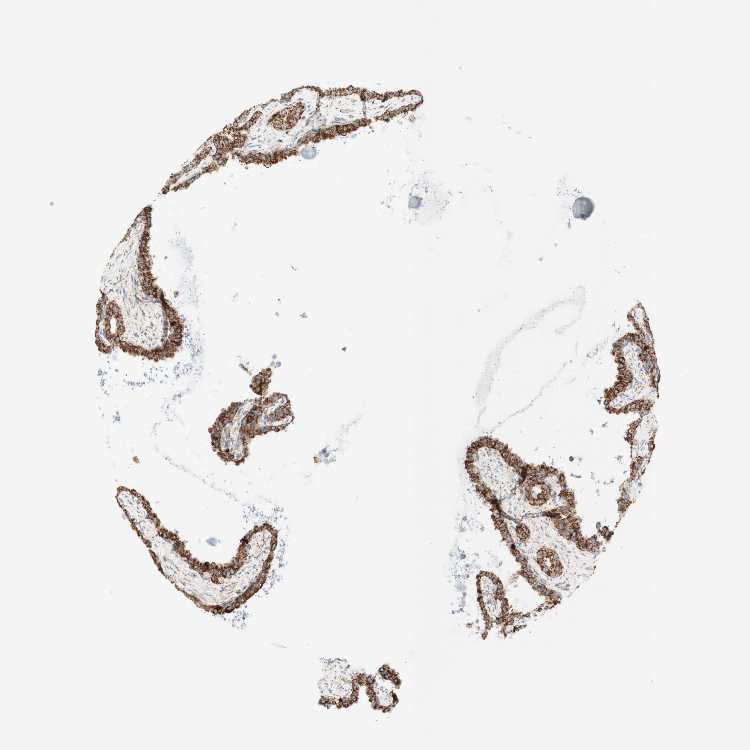

TISSUE PRIMARY DATA SEMINAL VESICLE Show tissue menu

SEMINAL VESICLE - Antibody stainingi

Antibody staining in the annotated cell types in the current human tissue is reported as not detected, low, medium, or high, based on conventional immunohistochemistry profiling in selected tissues. This score is based on the combination of the staining intensity and fraction of stained cells.

Each image is clickable and will lead to virtual microscopy that enables deeper exploration of all samples and also displays staining intensity scores, fraction scores and subcellular localization as well as patient and tissue information for each sample.

Antibody HPA011562Antibody CAB005585

Glandular cells HighHigh